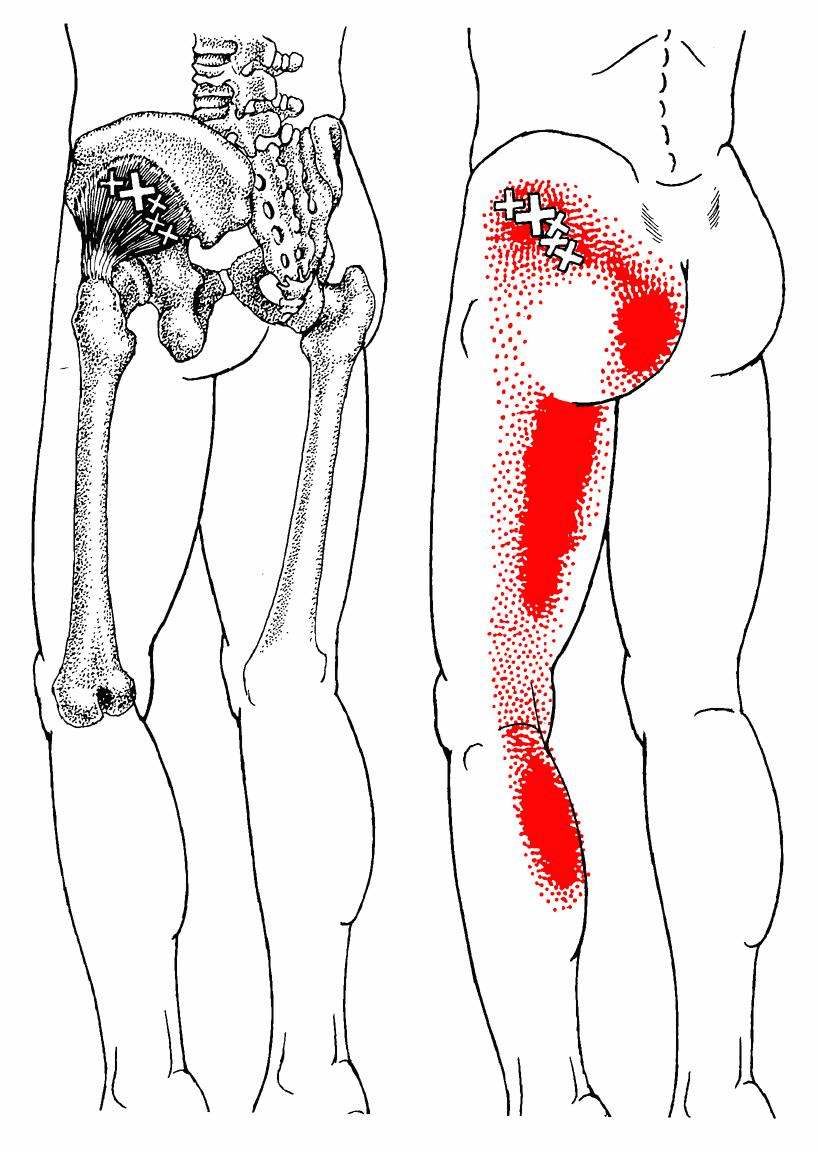

Pseudo-sicatica라고 칭하기도 하는데,

소둔근의 문제는 마치 좌골신경통과 같은 통증을 만들어 내기 때문입니다.

Ant.

Post. 소둔근의 Anterior part에 있는 TrPs에서의 방사통은 둔부 하외측 위와, 밑으로 대퇴의 측면, 무릎, 장딴지 및 발목으로 방사됩니다. Posterior fibers에 있는 trPs는 유사하지만 둔부의 하내측과 대퇴와 장딴지의 뒷 부분등 보다 후방으로 통증을 방사하는 경향을 갖습니다.

통증은 매우 고통스럽고 지속적인 양상으로 나타나며, TrPs의 위치가 깊이 위치하고 있고 원인 근육에서 매우 멀리 떨어진 곳에 통증이 나타나 TrPs를 찾기 어려운 경우가 많습니다.

앉아있을 때 보다 서있을 때 통증이 심화되는 경우가 많습니다.